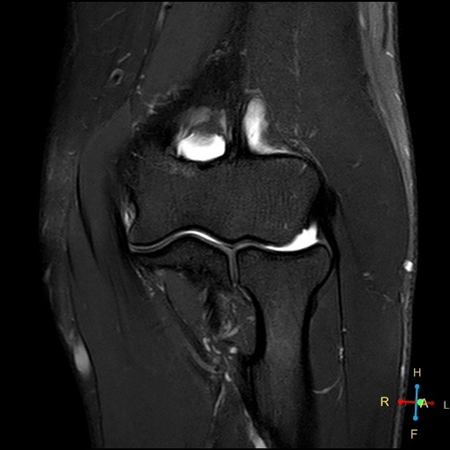

Coronal T2w SPAIR